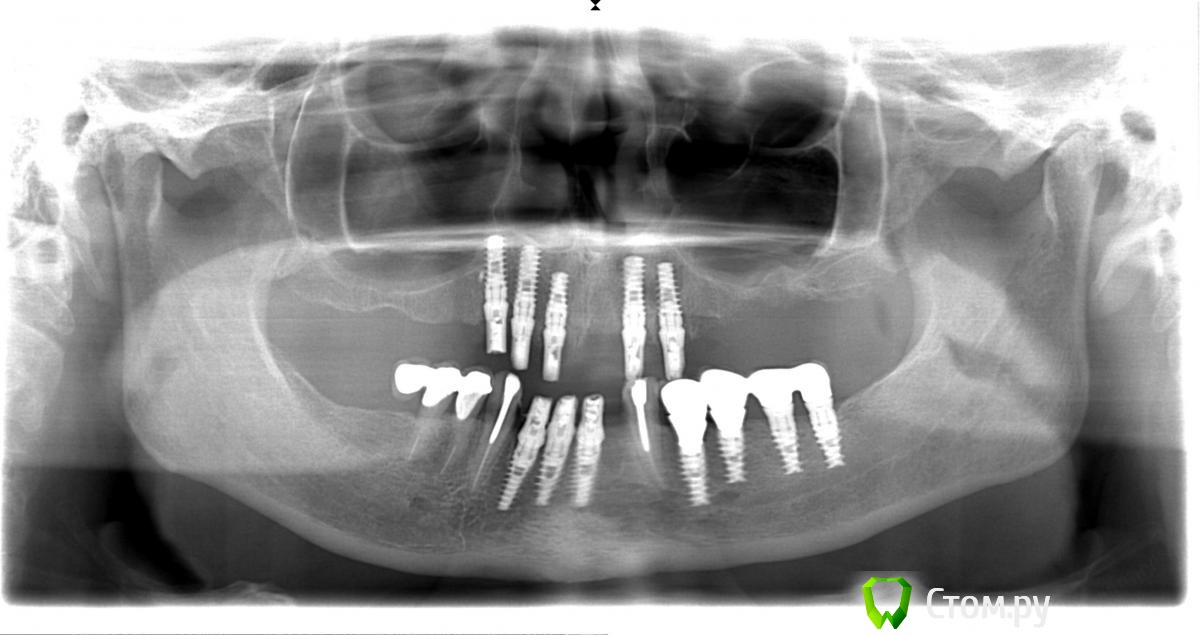

Troy Опубликовано 10 декабря, 2013 Поделиться Опубликовано 10 декабря, 2013 скорее всего плохо изолировали,придется выпиливать замки(те что в протезе),после сделайте следущее1- прокладки силикона не ставьте,а вместо них вырежте из целофана но не кольца а формы круга размером с монетку.2- приложите этот целофановый круг к абатменту и защёлкните его замком. так на все четыре3- уложите протез на протезное ложе,придерживая рукой,а другой рукой загоняйте материал в дырки которые высверлили.как заполнятся дырки, дайте больному закрыть рот в прикусе и подождите пока заполимеризуется.4- после этого протез снимется хорошо, и можете полировать.Спасибо большое. Пока думали что делать пациентка сутки носила протез. На следующий день он без проблем снялся. Вот кейс. Мои импланты и ортопедия. Один на верхней не выжил. Что скажете? Ссылка на комментарий

IvanK Опубликовано 10 декабря, 2013 Поделиться Опубликовано 10 декабря, 2013 На снимке 5 винтов, а на фото 4е?.. Ссылка на комментарий

Sir Edward'S Опубликовано 10 декабря, 2013 Поделиться Опубликовано 10 декабря, 2013 На снимке 5 винтов, а на фото 4е?..написано 1 не выжил Ссылка на комментарий

Sir Edward'S Опубликовано 11 декабря, 2013 Поделиться Опубликовано 11 декабря, 2013 Зачем жетогда локаторы, балки и кнопки придуманны? а какой смысл пациенту при 12 имплантах носить съёмник? 1 Ссылка на комментарий